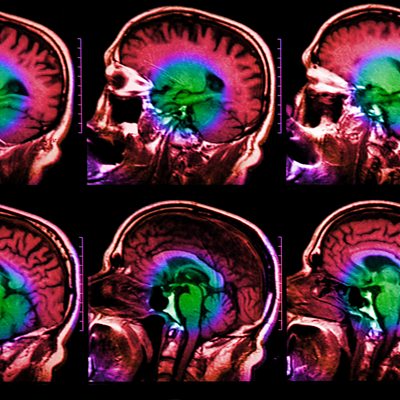

The latest findings in neuroscience are increasingly affecting the justice system in America. Owen Jones, professor of law and biology at Vanderbilt University, explores where neurolaw is making its mark and where the discipline is heading. One significant finding from MRI scanners is that the adolescent brain continues to develop right into the early- and mid-twenties. The fact that we are not ‘adults’ at age 18 is having big repercussions in the legal system. In San Francisco, the entire way that young offenders of crimes such as armed robbery up to the age of 25 are treated is adapting to the brain data. More and more, neuroscientists are testifying in courts, often to mitigate sentences including the death penalty in juveniles. Other times, they highlight rare brain abnormalities that cause violent and antisocial behaviour, which helps justify a lighter sentence. However, young brains are still malleable. In Wisconsin, brain imaging of juvenile prisoners can detect psychopathic markers. Once identified, staff can employ techniques to de-programme those antisocial traits and rehabilitate prisoners to ready them for, they hope, a crime-free life outside. And this is simply the first generation of neurolaw – where to next? (Photo: Human head scan, coloured magnetic resonance imaging (MRI) scan of healthy brain. Credit: Getty Images)